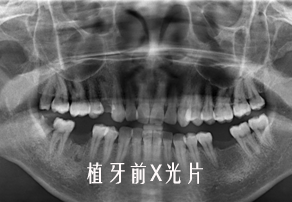

种植牙修复案例(四)

近些年来,人工种植牙固定牙已经被广大医生和患者所熟知,种植牙就和自己的牙齿一样,没有多余的钢丝,基托,也不用磨损旁边的好牙齿,是现下比较理想的修复方法。那么到底种植牙是怎么生长出来的呢?宁德中富口腔来告诉大家,人工种植牙的那些奥秘。